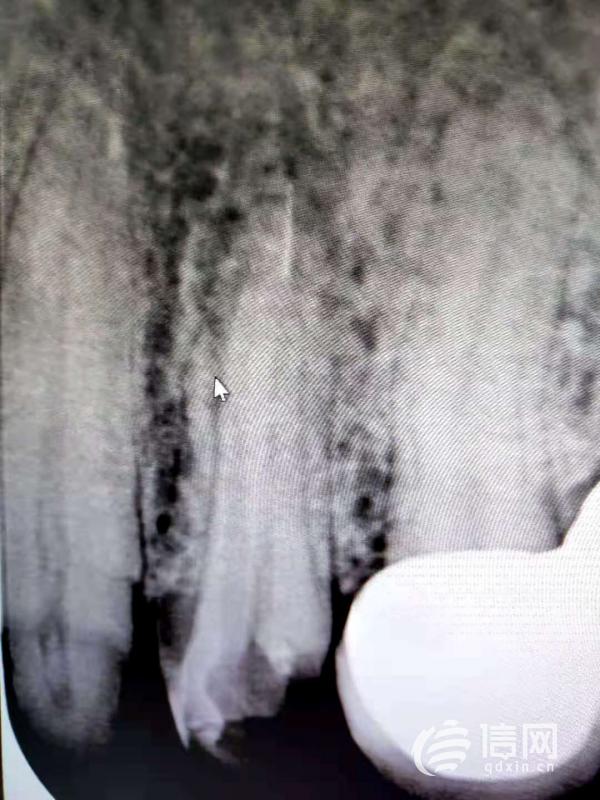

8月14日,张女士自己到了青岛市口腔医院进行检查。经检查,其中一颗牙的根管中留有一截针状异物,信网从她提供的CT结果上也清晰地看到了该段针状异物。“这是抽神经的时候,针尖断在了根管里,医生告诉我根管里面全都黑了,当时给出了几种治疗方案,但都很遭罪,我不得不选择拔掉这颗牙。”张女士说,在这颗牙的影响下,其他的牙齿也受到了影响,到现在她还戴着临时的牙套,无法正常咀嚼食物、疼痛等遭遇,给她的正常生活带来了巨大影响。